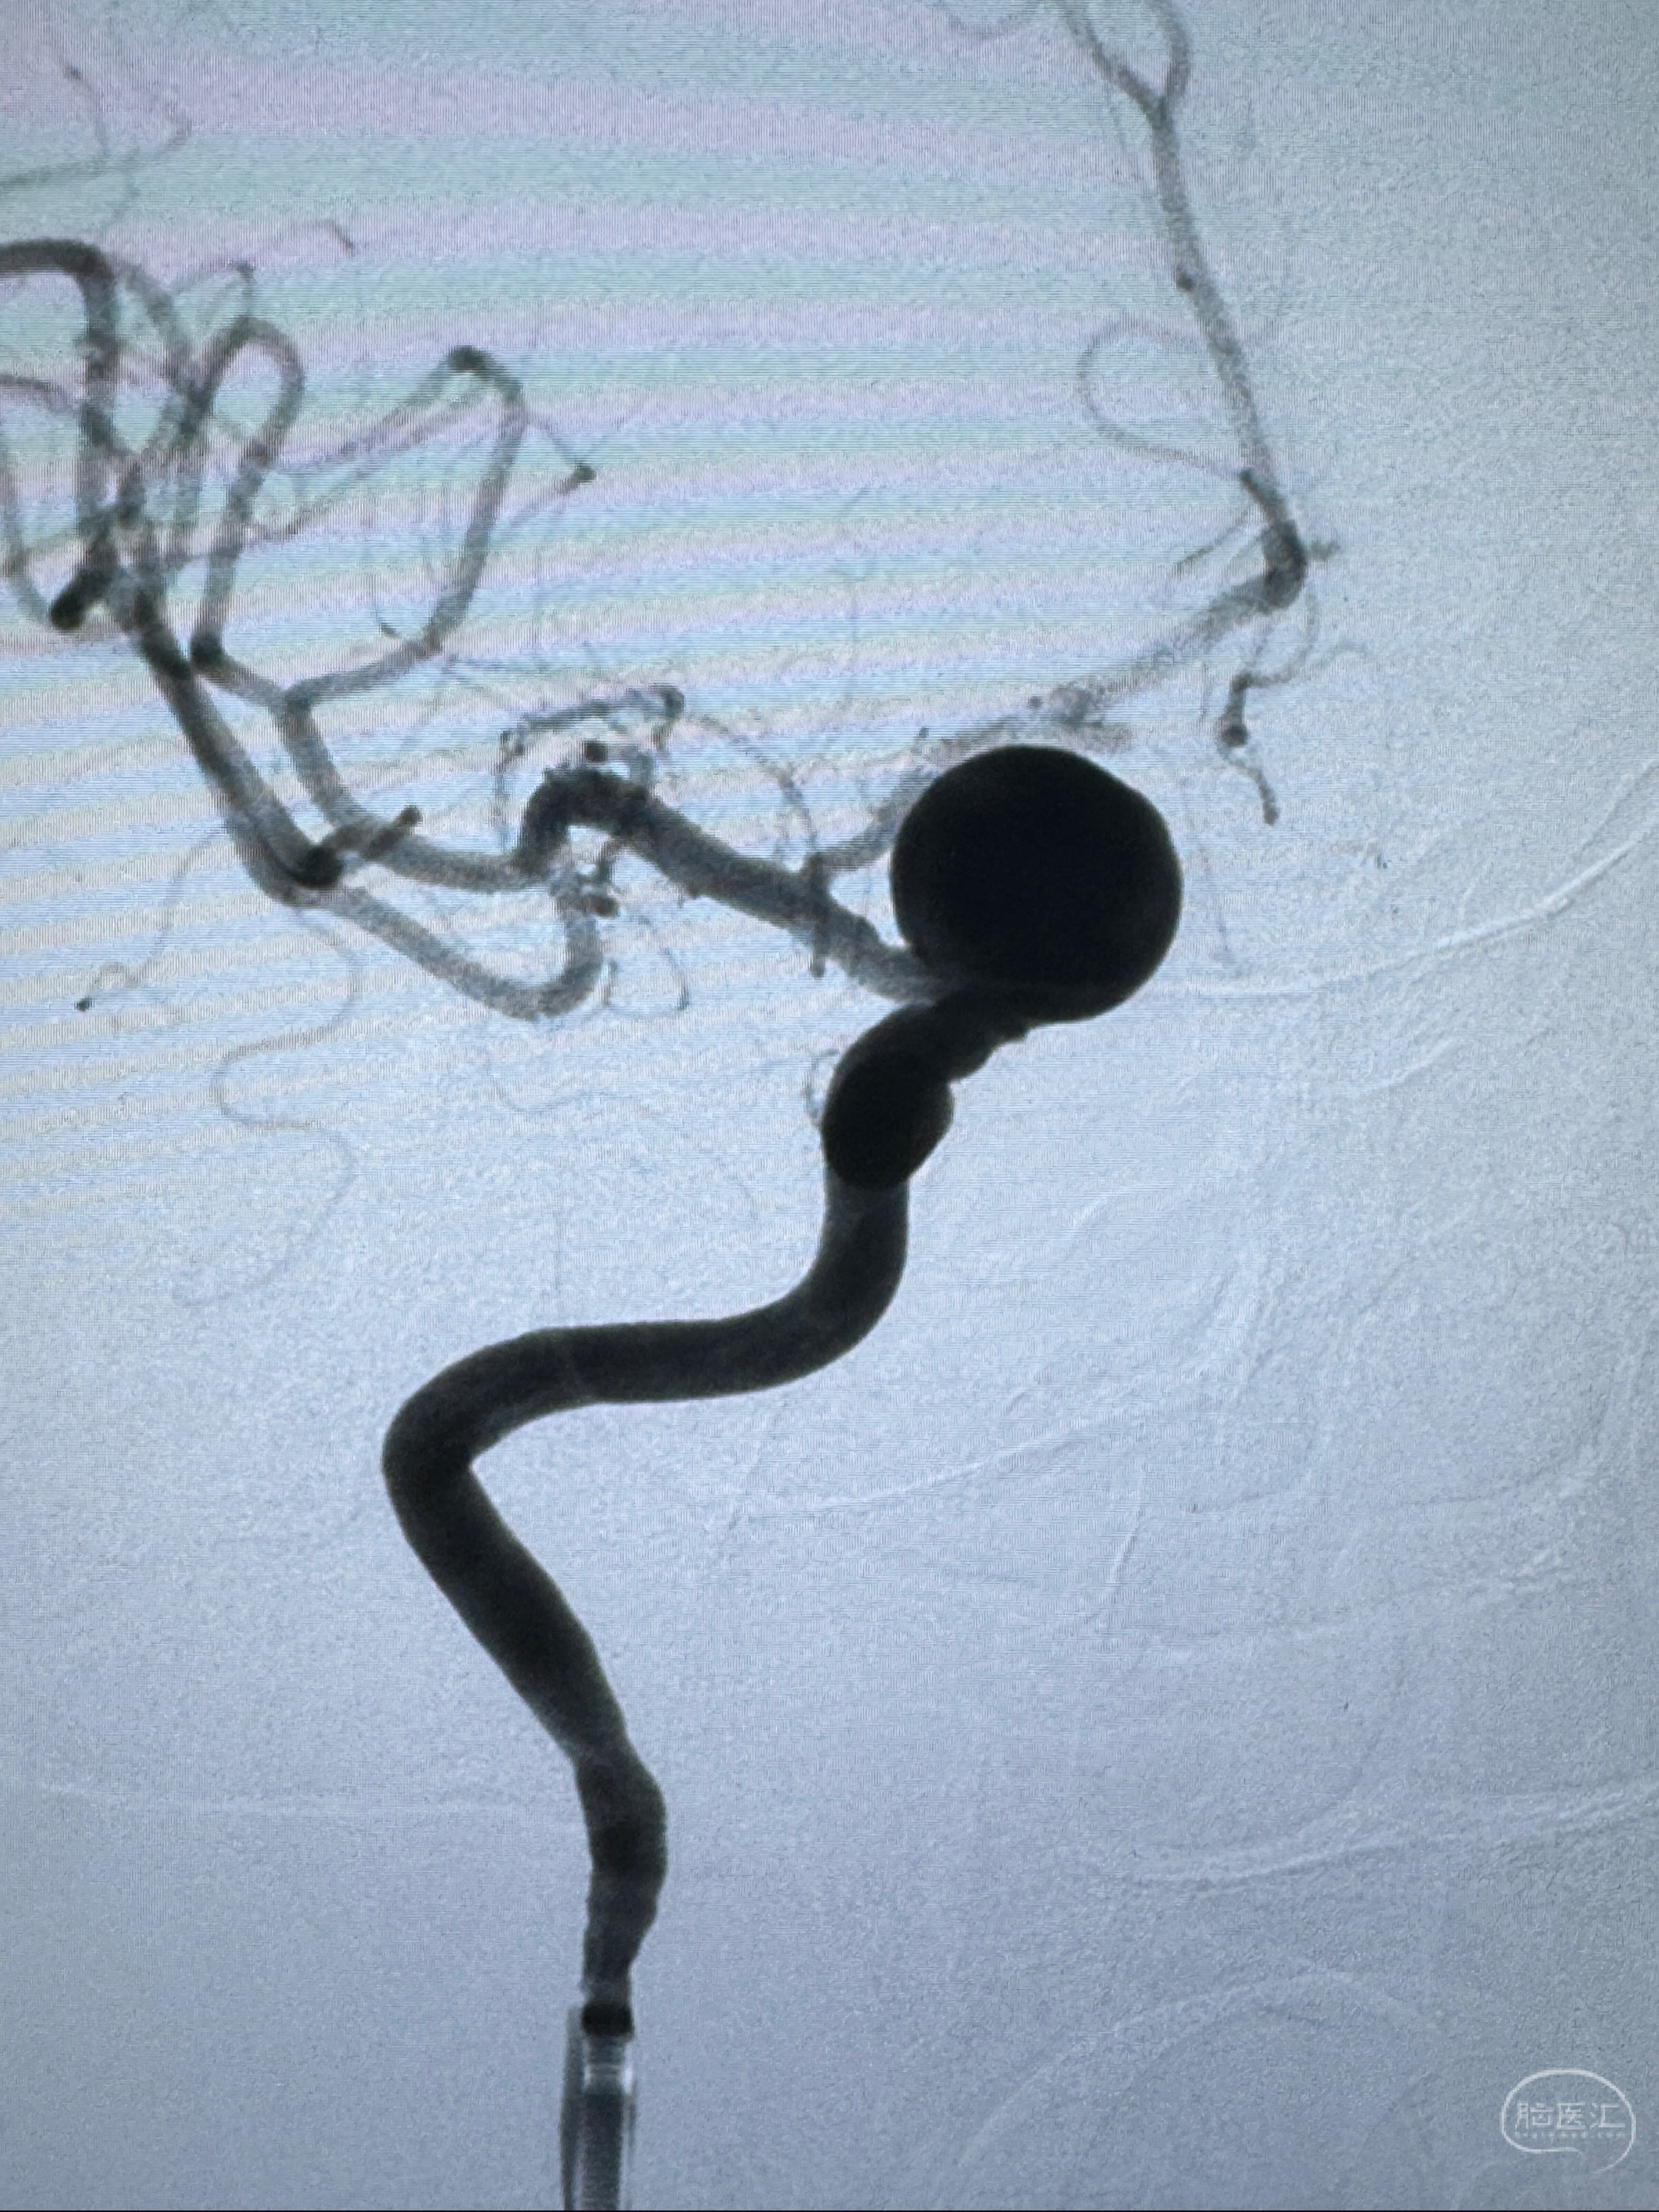

现病史:患者诉2年来反复发作性头痛,顶枕部为主,因自己考虑高血压可能,未予系统检查;患者约20日前无明显诱因下突发剧烈头晕,有天旋地转感,不能睁眼,伴视物模糊;外院查头颅MRI+MRA提示:左侧颈内动脉C6段动脉瘤;遂至复旦大学附属华山医院就诊,于2023-12-08行全脑血管造影提示:右侧颈内动脉C6段动脉瘤,瘤颈6.68mm,动脉瘤大小13.28*12.34mm,建议行密网支架辅助栓塞术治疗,因缺乏相关材料遂出院。现患者仍有顶枕部头痛不适,为求进一步诊疗脑血管病变至我科就诊,收治入院。

2023-12-08 复旦大学附属华山医院 全脑血管造影:右侧颈内动脉C6段动脉瘤,瘤颈6.68mm,动脉瘤大小13.28*12.34mm

2023-12-08外院DSA:右侧颈眼动脉瘤,约13*12mm大小,压颈试验显示左右向及后向前代偿可

测量动脉瘤的大小:16*13.8*7.6mm大小,较原先变大,考虑双抗后瘤内血栓溶解可能